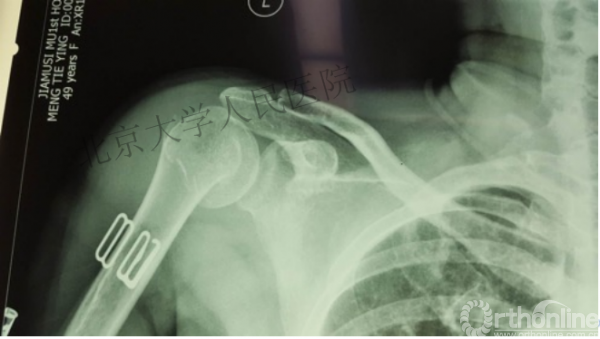

内侧皮质粉碎,低位外科颈骨折,肱骨头-干角维持困难。

术后复位丢失,肱骨头内翻畸形。

能否该偏心固定(钢板)为髓内固定,增加力臂?

此时对比髓内钉是不是有很大优势?